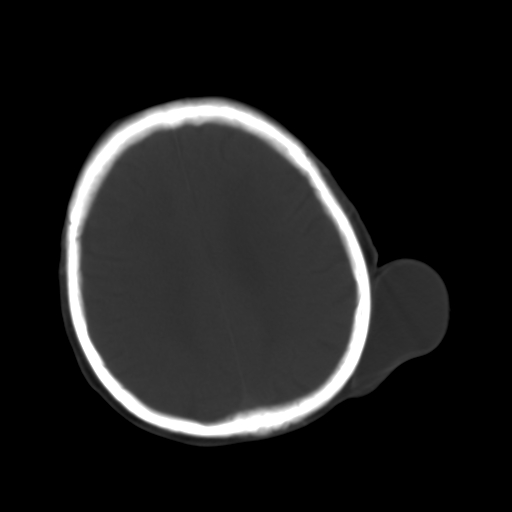

标题: CT25147:男,62岁,右侧肢体活动障碍不灵活三天。 [打印本页]

男,62岁,右侧肢体活动障碍不灵活三天,左侧头皮肿物十余年(ct值8hu)。

多发腔梗!皮下脂肪瘤!

1)多发性腔隙性脑梗塞。2)脑白质病。3)脑萎缩。4)左侧枕顶部头皮下皮样囊肿,不排除脂肪瘤。

1)多发性腔隙性脑梗塞。2)脑白质病。3)脑萎缩。4)左侧枕顶部头皮下皮样囊肿或表皮样囊肿。